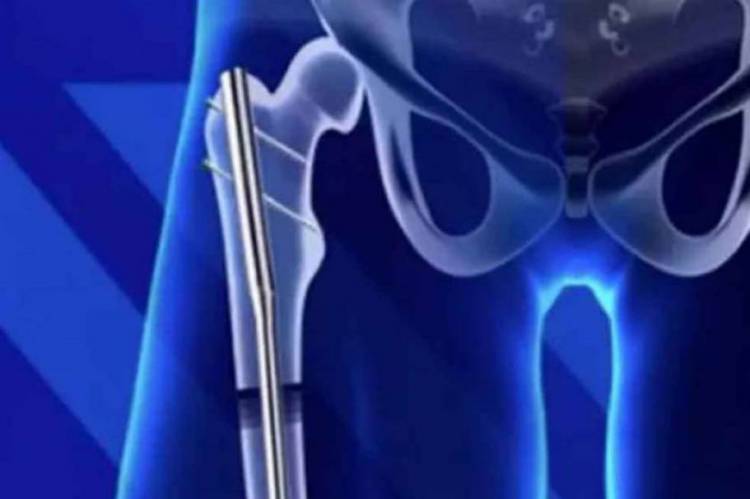

A cirurgia tem como objetivo realizar pequenas incisões na perna para ter acesso à parte oca do osso, onde uma haste eletrônica, controlada por um controle remoto externo, é inserida no membro. Os interessados precisam desembolsar aproximadamente US$ 75 mil para realizar o procedimento.

"Cortamos os ossos das pernas - fêmur (osso da parte superior da perna) ou tíbia (localizado na parte inferior do membro) e inserimos um dispositivo que os estica lentamente", afirmou o porta-voz da LimbplaxtX, em entrevista concedida ao portal da Austrália.

Ao esticar o membro, o paciente ficará mais alto gradativamente e de forma permanente, pelo menos é o que indicou os profissionais do instituto. O dispositivo é ajustado com a colocação de parafusos nas partes superior e inferior do osso. O procedimento é realizado em cada perna.